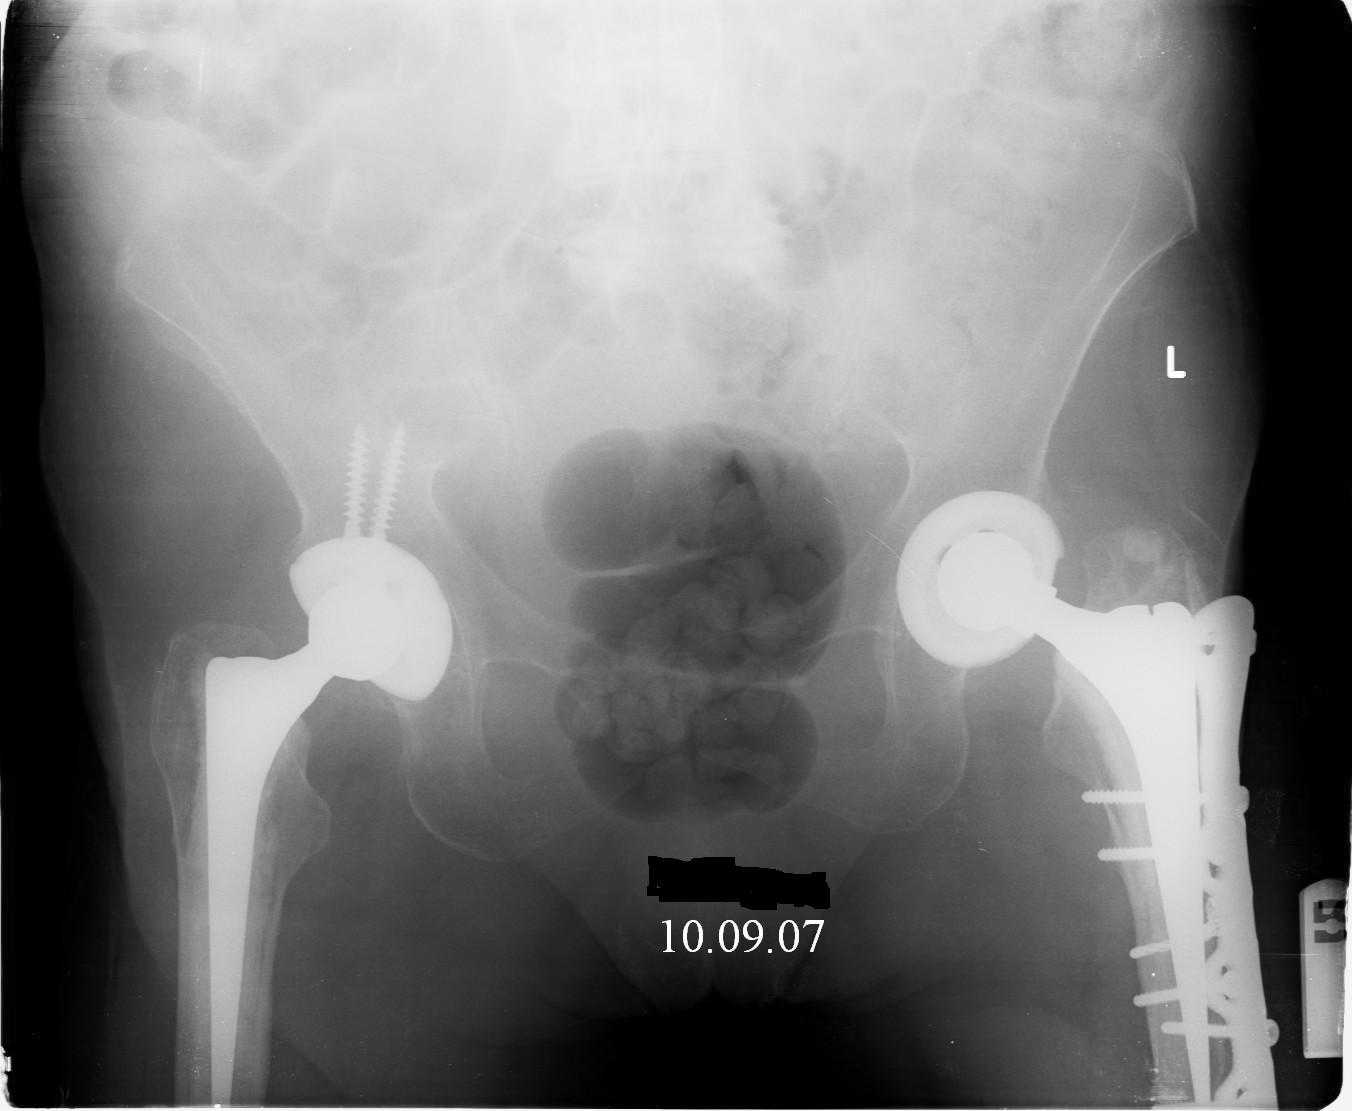

Re: Перипротезный перелом

Hello! This is just illustration in one of the choice of treatment